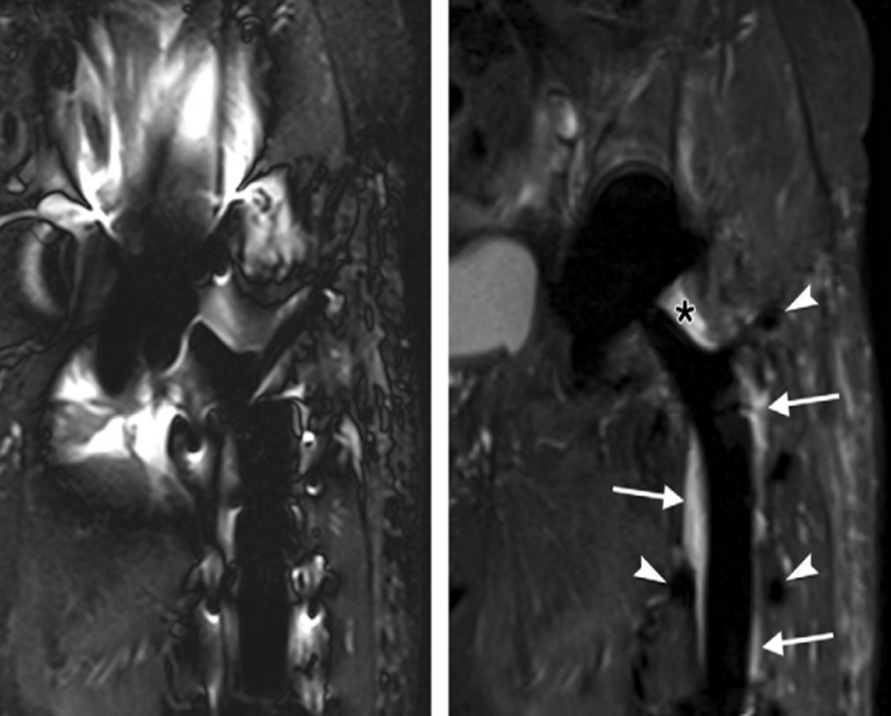

此外,该设备除常规磁共振检查外,对头颈血管壁高分辨率分析、心脏形态及功能的无创性检查也达到了相当高的水准。不仅大幅度提高病人心脏扫描的舒适性,而且保证极高心脏成像质量。

△微米成像等

△SEMAC第三代去金属成像(右)